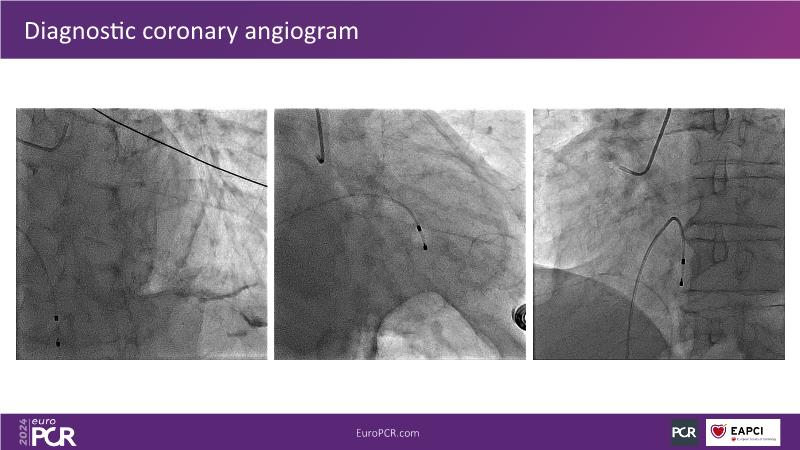

Tune into this 2024 session for insights into the latest ESC guidelines, strategies to prevent and treat no reflow, and an examination of trials like TASTE, TAPAS, and TOTAL on coronary thrombus management. Explore also the outcomes of the CHEETAH study, pondering a potential paradigm shift, and delve into a case study on thrombus removal in a patient with high thrombus burden.